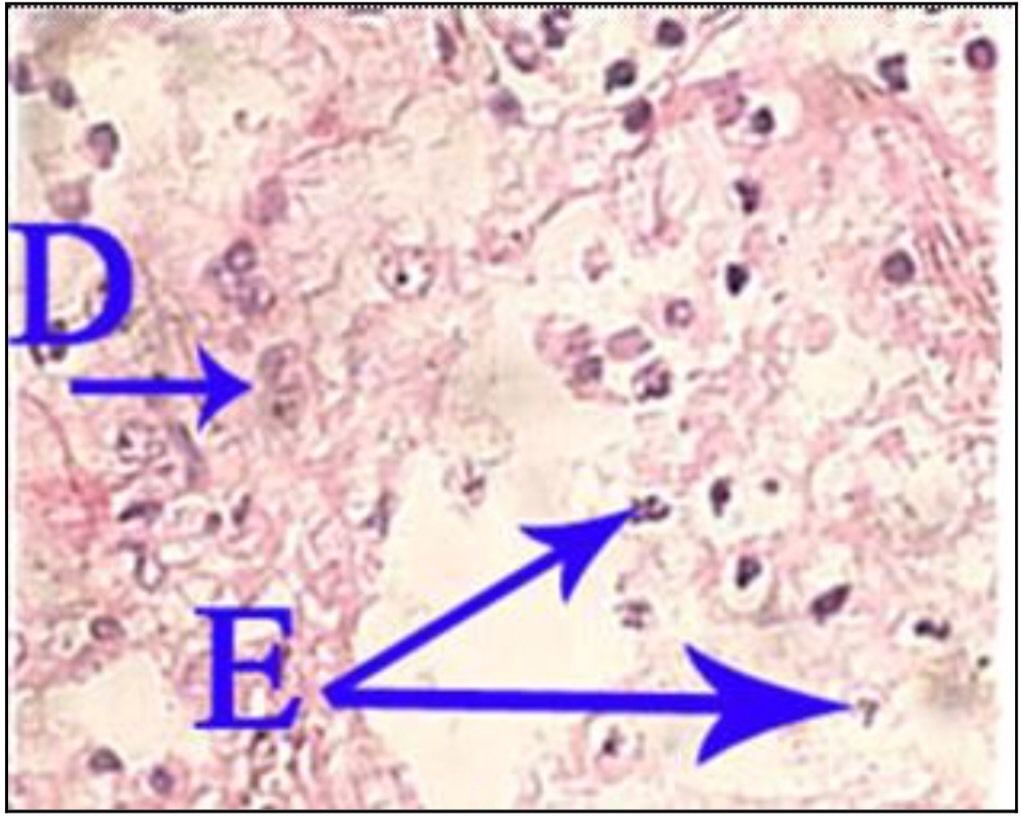

Question 5

Question

What is the correct answer at point E?

Answer

• - épithélium exocervical normal

• - membrane basale

• - cellules anormales

• - épithélium dysplasique sévère

• - massifs carcinomateux

Question 6

What is the correct answer at point D ?